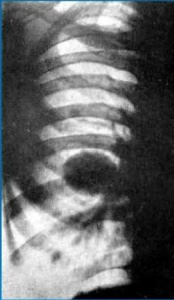

Фаза крупнофокусного распада — результат слияния мелких полостей в более крупные. Внутренние контуры более крупных полостей подрыты, бухтообразны, фестончаты.

Опухолевый узел сохраняет шаровидную форму и бугристые контуры (рис. 3.4, а, б).

Вторым подвидом этой фазы распада является образование одной эксцентрично расположенной полости. При прогрессировании краевой распад как бы окаймляет ядро опухолевого узла (рис. 3.5). При бронхографии очень редко удается заполнить полость распада.